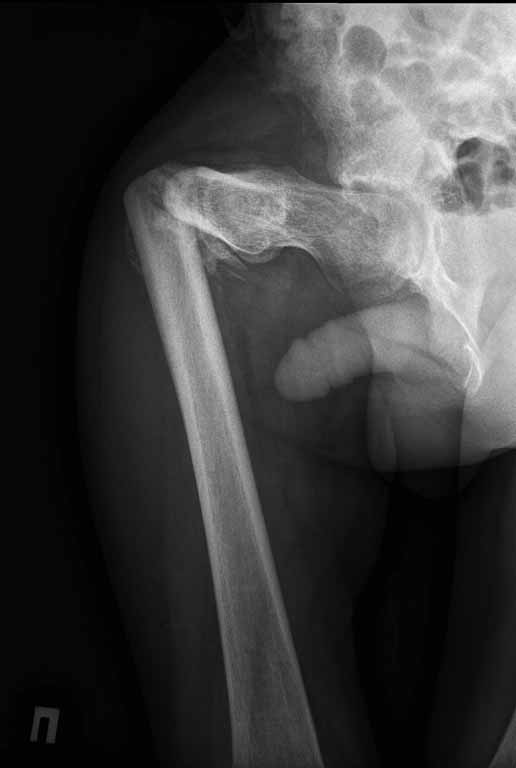

На лечении находится пациент с тяжелой сочетанной травмой. На сегодняшний день встал вопрос о тактике лечения переломов бедер( по месту жительства бедрами не занимались).

Пациенту 22 года. Травма в июле 2010г, лечился в районной больнице. К нам попал в апреле 2011г. Тяжелая сочетанная травма (29.07.2010): тупая травма живота с повреждением внутренних органов. Закрытая травма грудной клетки с переломом ребер. Пневмоторакс справа. Тяжёлая позвоночно-спинномозговая травма. Закрытый осложнённый переломо-вывих С5 позвонка. Верхний парапарез, нижняя параплегия, нарушение функции тазовых органов по типу недержания. Цекостома. Пролежень левой ягодичной области. Неправильно консолидированные переломы верхних третей обеих бедер. Застарелый вывих левого бедра. Осложнение: Поддиафрагамльный абсесс слева, забрюшинного пространства. Свищ желудка и ободочной кишки. Синегнойный сепсис. Двухстороняя пневмония. Но это уже анамнез. Пациент был неоднократно оперирован на органах брюшной полости и осложнениями с ними связанными.

В ягодичной области слева глубокий пролежень размером 2х2см, дном является вывихнутая головка бедра. Неврологически в нижних конечностях динамика положительная, появились движения в правой стопе, чувствительность в стопах. По переломам бедер: подвижности в местах переломов нет, снимки высылаю.

Уважаемые коллеги, помогите определиться с оптимальной тактикой в лечении перелома бедер. Степень оснащенности у нас достаточная (аппараты, штифты, пластины, ЭОП).

Планирую начать с правого бедра, ЧКО таза (передняя рама) с фиксацией бедра. О/клазия места перелома правого бедра и устранение грубых смещений в аппарате. окончательно можно оставить и в аппарате. Далее аппаратное устранение вывиха левого бедра.